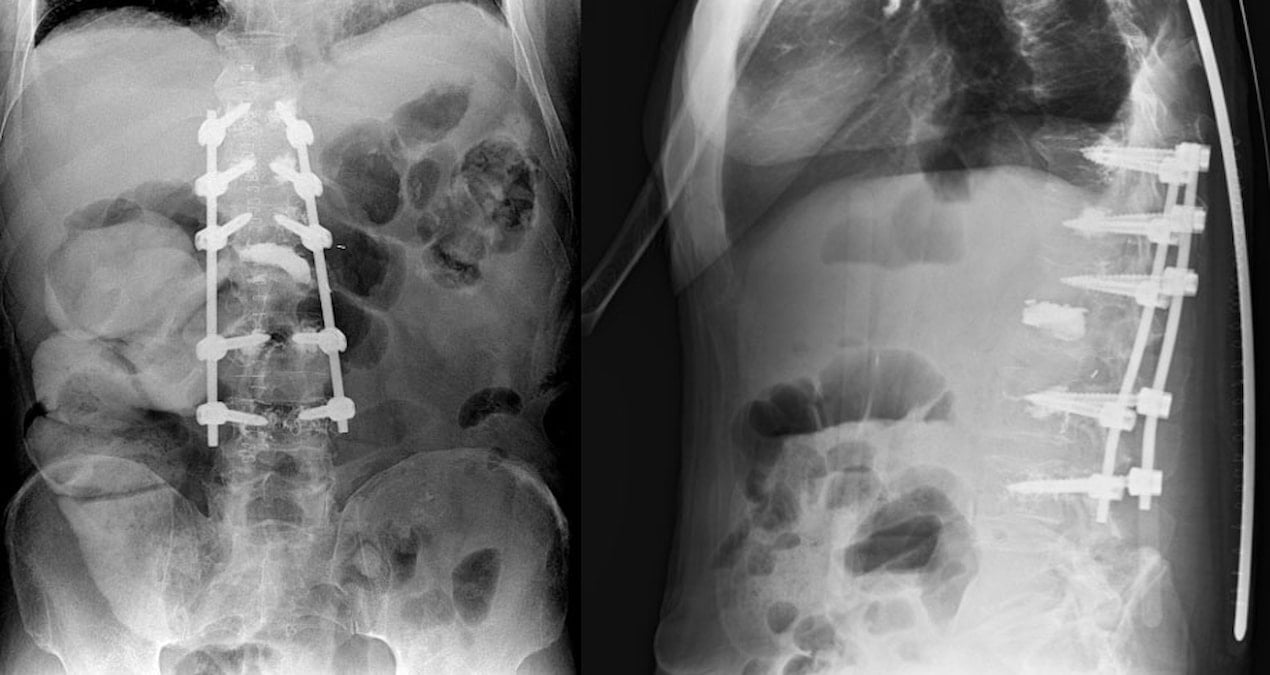

Yapılan detaylı tetkikler sonucunda cerrahi müdahale kararı alınan Doğan’ın bir böbreğinin tümörle birlikte 8,5 kilograma ulaştığı belirlendi.

“Normalde bu tür ameliyatlarda karın içine girilerek periton adı verilen karın zarı açılır ve bağırsakların bulunduğu alanda çalışılır. Bu durum ameliyat sonrası bağırsak yapışıklığı, yeniden ameliyat gereksinimi, bağırsak hareketlerinin geç başlaması ve hastanın 3–4 gün burundan takılan mide sondasıyla takip edilmesi gibi sorunlara yol açabilir. Biz bu ameliyatı karın boşluğuna ve bağırsaklara girmeden gerçekleştirdik. Bu sayede hastanın bağırsak fonksiyonları daha hızlı düzeldi, ameliyat sonrası toparlanma süreci kısaldı, yatış süresi azaldı ve hasta çok daha erken dönemde beslenip mobilize olabildi.”